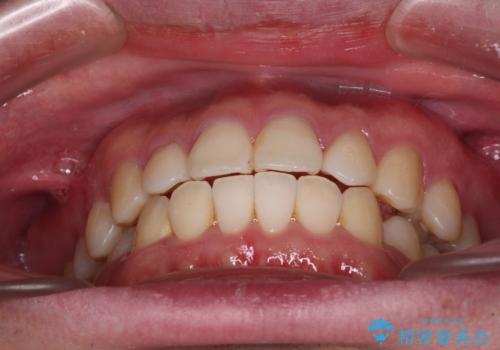

インビザラインで奥歯の咬み合わせと前歯のデコボコを改善

- 前歯のデコボコと奥歯の咬み合わせを気にして来院された患者様です。

前歯のデコボコはインビザラインで十分に対応可能と判断できましたが、咬合力が強いため、臼歯(特に右側)の交叉咬合はインビザライン単体では困難と思われました。

インビザライン単体では右側の交叉咬合を解消することができなかったため、アンカースクリューを併用して咬合を改善させました。